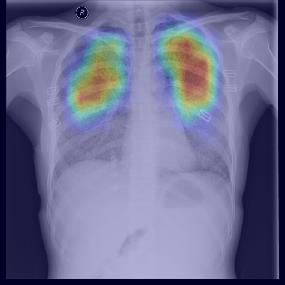

Chest X-ray (CXR) is the most typical diagnostic X-ray examination for screening various thoracic diseases. Automatically localizing lesions from CXR is promising for alleviating radiologists' reading burden. However, CXR datasets are often with massive image-level annotations and scarce lesion-level annotations, and more often, without annotations. Thus far, unifying different supervision granularities to develop thoracic disease detection algorithms has not been comprehensively addressed. In this paper, we present OXnet, the first deep omni-supervised thoracic disease detection network to our best knowledge that uses as much available supervision as possible for CXR diagnosis. We first introduce supervised learning via a one-stage detection model. Then, we inject a global classification head to the detection model and propose dual attention alignment to guide the global gradient to the local detection branch, which enables learning lesion detection from image-level annotations. We also impose intra-class compactness and inter-class separability with global prototype alignment to further enhance the global information learning. Moreover, we leverage a soft focal loss to distill the soft pseudo-labels of unlabeled data generated by a teacher model. Extensive experiments on a large-scale chest X-ray dataset show the proposed OXnet outperforms competitive methods with significant margins. Further, we investigate omni-supervision under various annotation granularities and corroborate OXnet is a promising choice to mitigate the plight of annotation shortage for medical image diagnosis.